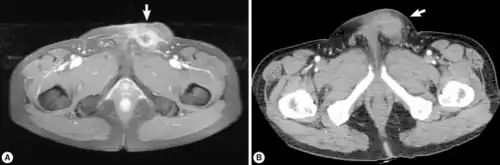

Infection of S. erinaceieuropaei is termed sparganosis.[8] However, this term encompasses the entire genus Spirometra and is not specific to S. erinaceieuropaei. Sparagnosis due to S. erinaceieuropaei is rare.[9] Adults Spirometra typically infect dogs, cats and other carnivores.[16] They will reproduce in their intestines, and the eggs will be shed in their feces.[17] Although humans can get infected with this parasite, they cannot contract it from the feces of an infected cat or dog.[18] Sparagnosis refers specifically to the infection with Spirometra larvae and is endemic in animals but a rare condition for humans.[8] In humans, the larvae are typically found in subcutaneous tissues or muscle, and will form slowly growing masses.[16] Sometimes infection in humans can also involve genitourinary tract, pleural or abdominal cavity, and scrotum. Infection can also involve the central nervous system, but this is even less common. When the central nervous system is involved, symptoms may occur as many as twenty years after infection.[19] These can include weakness, headache, seizures, numbness, tingling, or abnormal skin sensations.[16] Because the masses are typically slow growing, they often resemble tumors on radio graphs.[19] Additionally, larvae may create migratory lesions (also called wandering lesions) within tissue. These lesions are a large sign of infection.[19]

Infection in humans can be detected via imaging, but because larvae may appear as a mass, most diagnosis occurs after surgical removal.[16][8][9] Diagnosis in animals is typically done by characterizing eggs in fecal matter. Since most tapeworm infections within the genus Spirometra have similar egg morphology, species characterization is not typical. Animals are usually treated with anti-worm medications, such as Praziquantel.[10] Surgical removal is the most common treatment in humans, as well as treatment by anti-worm medication such as Albendazole.[11]